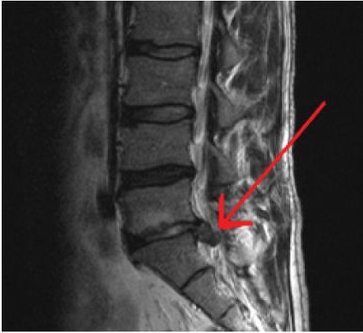

그 허리통증 원인을 특정할 수 있고 많이 알려진 허리 질환인 요추추간판헤르니아가 바로 허리 디스크 입니다. 척추뼈 사이에 있는 추간판이 망가져서 그 안에 있는 젤라틴 같은 디스크가 탈출되어 신경을 압박하면서 통증이 나타납니다.

추간판 이라 불리는 곳은 수분이 많이 함유된 젤리 모양의 수핵과 그것을 둘러싸고 있는 연골조직으로 이루어져 있습니다. 이들은 요추에 가해지는 압력을 분산시켜 충격을 완화해주는 쿠션 역할을 해 주고 있습니다. 그런데 연골조직이 탄력을 잃고 작은 균열이 생기면서 수핵의 일부가 밖으로 탈출하게 됩니다. 그래서 허리 디스크 질환을 추간판 탈출증이라고 합니다.

밖으로 밀려난 수핵이 신경을 압박해서 허리 통증이 생기는데 이 상태를 방치하게 되면 수핵이 점점 더 밖으로 밀려나와 통증과 저리는 증상이 심해집니다. 허리 디스크와 협착증의 차이 중 눈에 보이지는 않지만 발생 원인과 연령대가 다르다는 점이 가장 크다고 할 수 있습니다.